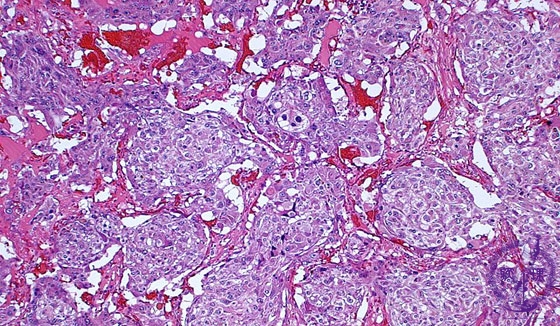

Microscopic findings (HE stain, middle power of view). The tumor cell nests surrounded by fibrovascular septa (also termed as gZellballenh), represent the characteristic architectural pattern of pheochromocytoma or intraadrenal parganglioma.